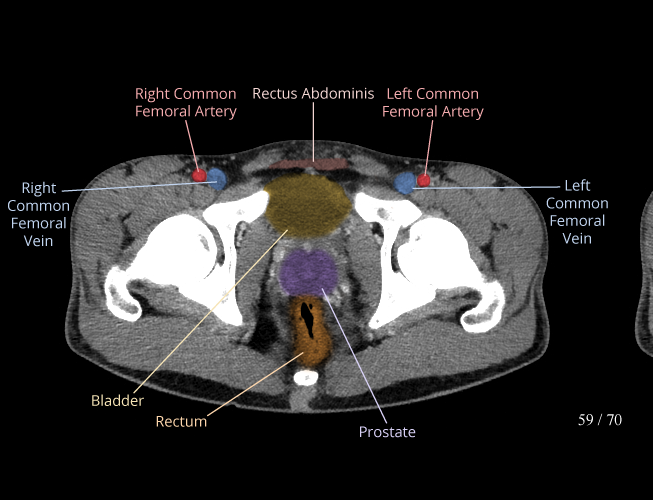

Body

Covers abdominal CT anatomy.

Pelvis

Covers pelvic MRI anatomy.